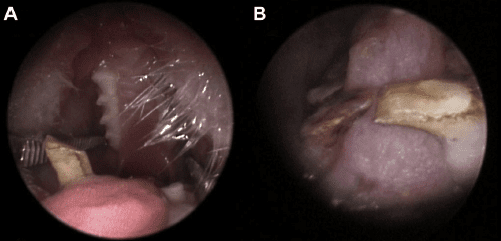

Troubles des prémolaires et molaires chez les degus.

(A) Allongement coronal avec formation d’éperons de la première dent de la joue mandibulaire droite.

(B) Allongement coronal bilatéral de la première dent prémolaire mandibulaire, avec formation typique d’un éperon mandibulaire, d’un « pont » et piégeage ultérieur de la langue. (Vladimir Jek)